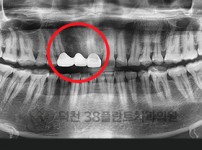

치료전후